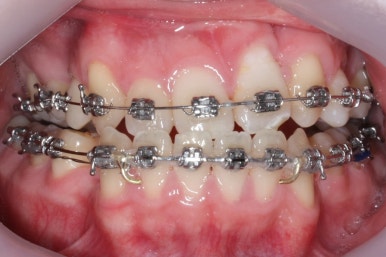

부산구순구개열 키다리아저씨치과에 처음 오셨을 때의 입 안의 모습입니다.

입천장이 갈라져서 어릴 때 봉합 수술을 했기 때문에 그 상처가 굵게 남아있는 것을 볼 수 있습니다. 일반적으로 피부상처도 다른 부위보다 단단하듯이 입천장의 봉합 상처도 매우 단단하게 아물기 때문에 성장에 방해를 주게 됩니다.

가로폭이 매우 좁고 찌그러져 있습니다.

또한 위턱이 앞으로 자라나는 것도 방해해 대부분 앞니가 거꾸로 물리게 됩니다.

또한 가랄져 있던 선에 걸쳐 있는 영구치 일부는 선천결손이 되는 경우가 많습니다.

이번 환자분도 이런 특징을 모두 갖고 계셨습니다.